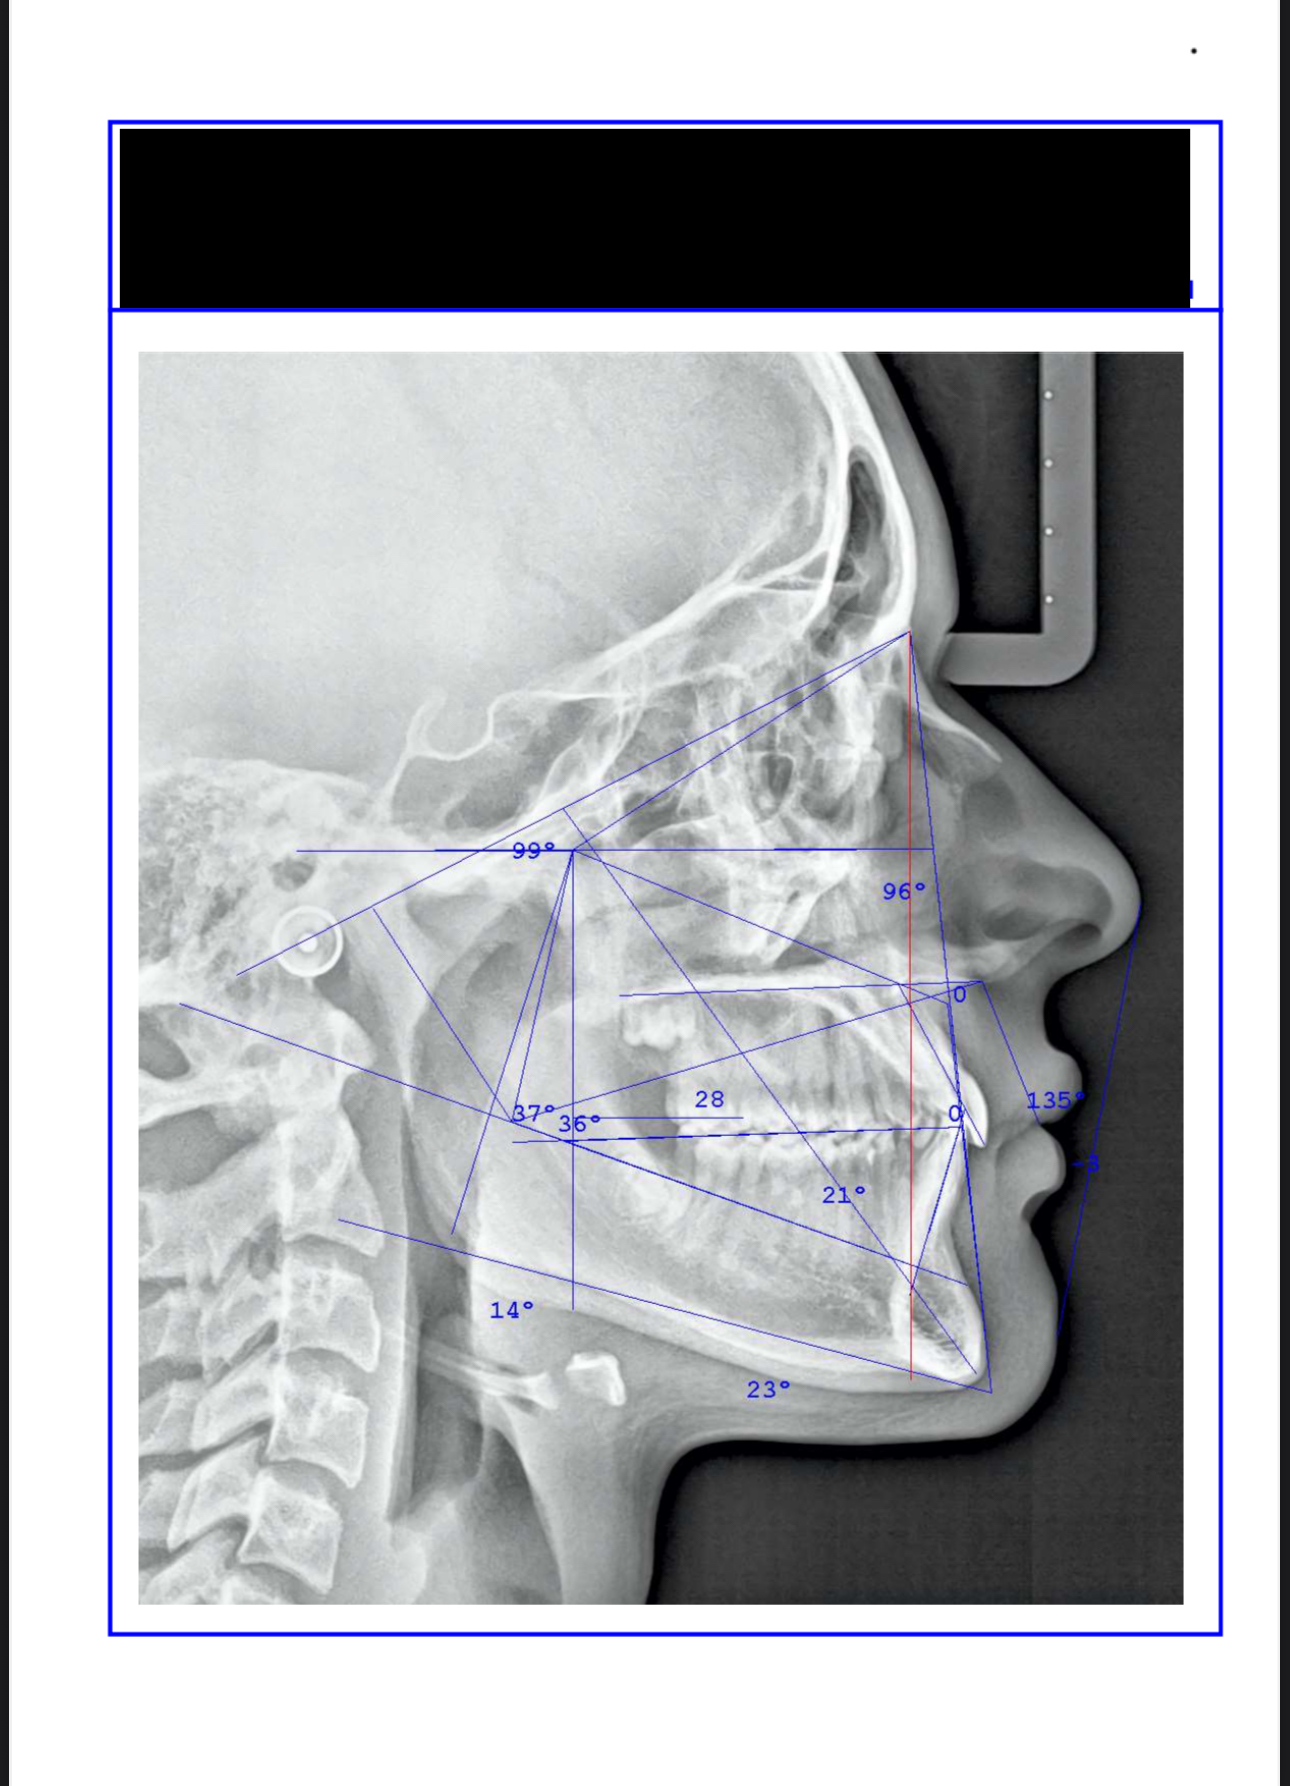

just made a few scans and im considering palete expander of face mask, ideally both?

IMG 7914

i was thinking of:

Rapid Palatal Expander (RPE) + generic face mask

any other tip/recommendation is highly appreciated